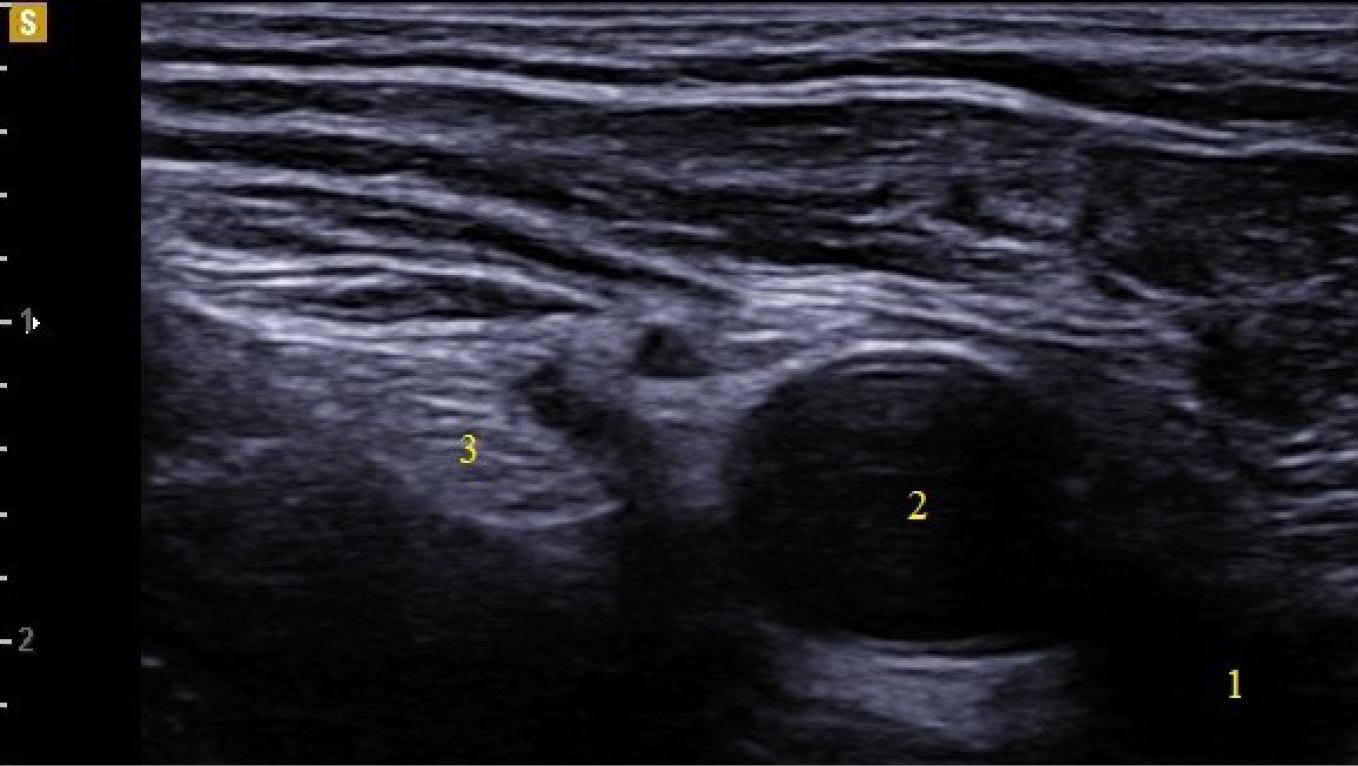

To mitigate the probability of technical complications, regional anesthesia was performed by the same anesthesiologist with expertise in ultrasound-guided regional anesthesia and nerve catheterization. The femoral nerves were catheterized aseptically via the ultrasound-guided technique using a Samsung HM70 Ultrasound System (Samsung Medical, South Korea) and a sterile, disposable Kontiplex Tuohy continuous peripheral nerve block catheter set (B. Braun, Germany). A 15 MHz linear transducer was positioned on the femoral crease to visualize the femoral artery, vein, and nerve (Fig. 1).

Fig. 1. Ultrasound image of the femoral nerve.

Note. 1 — femoral vein, 2 — femoral artery, 3 — femoral nerve.